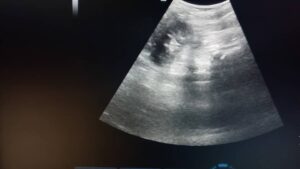

الدكتور محسن طراف (اختصاص جراحة بولية) قال :تمكن الفريق الطبي الاختصاصي من إصلاح تمزق كلية رضي لمريض عمره 12 سنة,وأضاف : راجع المريض المشفى بشكوى ألم خاصرة يسرى مع انتفاخ فيها وتبين لنا بعد إجراء الفحص السريري وجود انتباج بالخاصرة اليسرى مع رج قطني إيجابي أما العلامات الحيوية طبيعية و تبين بعد صورة الايكو وجود كلية يسرى صغيرة الحجم مع وجود سائل حر صافٍ بقدر 2 لـ حولها، الكلية تبدو مقسومة لجزئين جزء علوي و جزء سلفي مع تجمع سائل كبير بينهما وبين التصوير الطبقي المحوري تمزق القطب السفلي للكلية اليسرى مع وجود ورم دموي كبير ,,,و أكد انه بعد سؤال المريض تبين وجود قصة رض على الخاصرة اليسرى منذ شهر ونصف راجع على أثرها مركز طبي وكانت النتيجة وجود ورم دموي تحت محفظة الكلية اليسرى مع تمزق بالكلية، خضع المريض على أثرها للدراسة والمراقبة داخل ذلك المركز و تخرج متحسناً وأوضح أنه تم تحضير المريض للدراسة والاستقصاء.

و إجراء بزل الورم و خروج سائل صافي ( بول) دون وجود دم، تم إرسال عينة للتحليل.. بعدها تقرر إجراء عمل جراحي لفتح الخاصرة اليسرى.. وخلال العمل الجراحي تأكد وجود تمزق بالكلية مع انفصال القطب السفلي للكلية اليسرى و وجود ناسور يمتد من الكؤويسات السفلية ، تم إجراء استقصاء الحالب و استئصال القطب السفلي المفصول عن الكلية و تركيب قثطرة بالحالب وإغلاق شق الأجواف المفرغة مع تركيب مفجر..